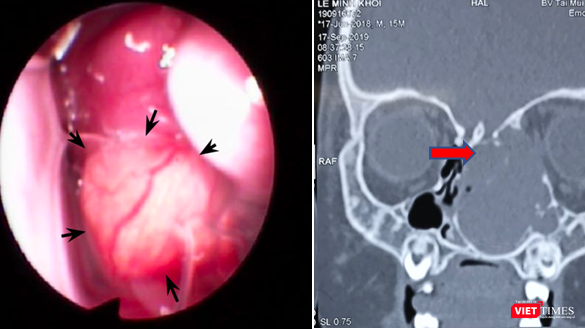

![]() |

| Hình ảnh nội soi và CT scan khối u lớn vùng hốc mũi trái. Ảnh: BVCC |

Tại BV Tai Mũi Họng TP.HCM, bác sĩ tiến hành các xét nghiệm và đã chẩn đoán vùng hốc mũi trái của bé có khối u kích thước khoảng 35mm. Khối u này gây biến dạng, hủy xương sàng, xương thành trong hốc mắt và một phần mềm sọ, đồng thời, khối u đè ép các cấu trúc hốc mũi, chèn ép đỉnh hốc mắt và hậu nhãn bên trái.

Đây là trường hợp khó do khối u nằm ở sát nền sọ nên nguy cơ chảy dịch não tủy trong lúc phẫu thuật là rất cao.